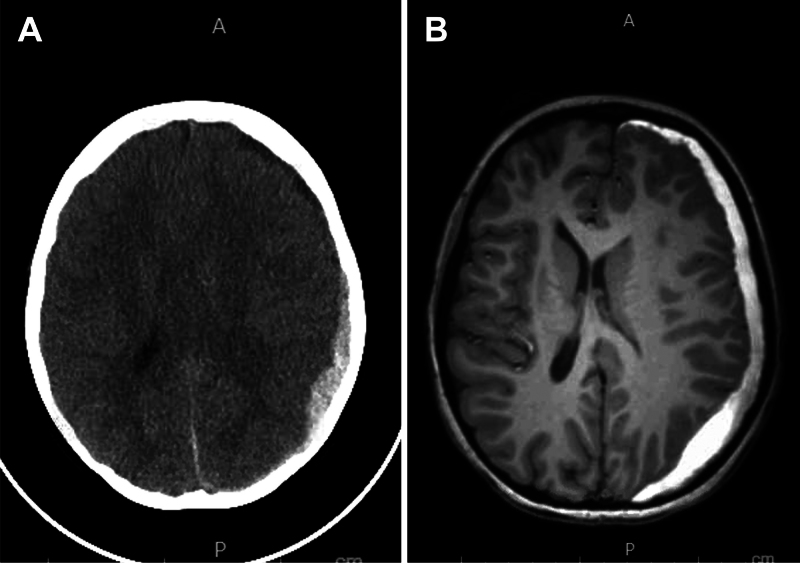

Observations: An 11-year-old male with newly diagnosed acute myeloid leukemia developed persistent, postural headaches following a lumbar puncture performed for diagnostic and therapeutic purposes. Initial imaging revealed a moderate left-sided SDH with midline shift, yet MRI of the lumbar spine failed to demonstrate an obvious CSF leak. Conservative management did not alleviate symptoms. Given the clinical picture of low CSF pressure, an EBP was administered, resulting in immediate headache improvement and subsequent radiographic evidence of SDH resolution.